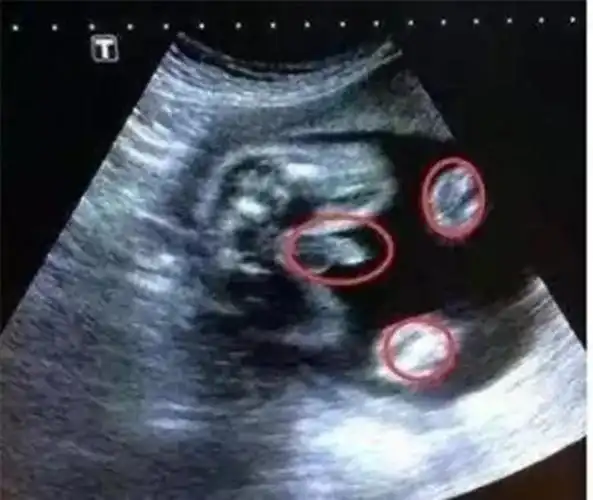

男女胎儿b超发育全过程高清图

b超单上3个数据,或许暗示胎儿性别"秘密",看不懂的孕妈好可惜